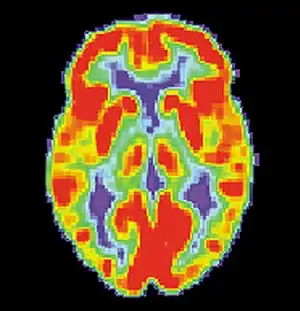

Neural systems used by procedural memory are commonly targeted by Human Immunodeficiency Virus; the striatum being the structure most notably affected.[64] MRI studies have even shown white matter irregularity and basal ganglia subcortical atrophy in these vital areas necessary for both procedural memory and motor-skill.[65] Applied research using various procedural memory tasks such as the Rotary pursuit, Mirror star tracing and Weather prediction tasks have shown that HIV positive individuals perform worse than HIV negative participants suggesting that poorer overall performance on tasks is due to the specific changes in the brain caused by the disease.[66]